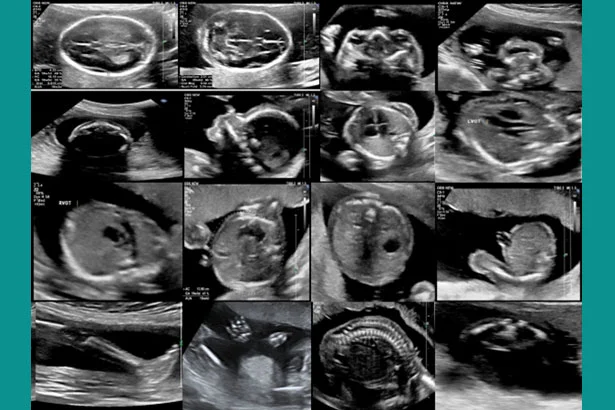

Our expert, Dr. Neha Gupta, is a highly qualified fetal medicine specialist. She has many years of experience in doing ultrasounds during pregnancy. She is not only trained in detection of abnormalities in the unborn child but will also counsel you how to approach further in the pregnancy. She is experienced in counseling the families in whom the future pregnancies (the unborn child) are at risk of developing hereditary diseases or helping those women who have some medical disorders which can affect the baby in the womb.